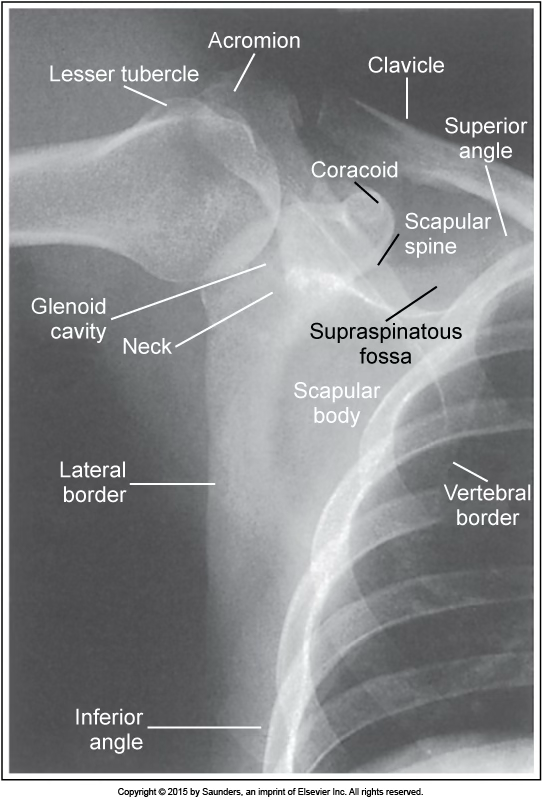

AP scapula

accurate positioning